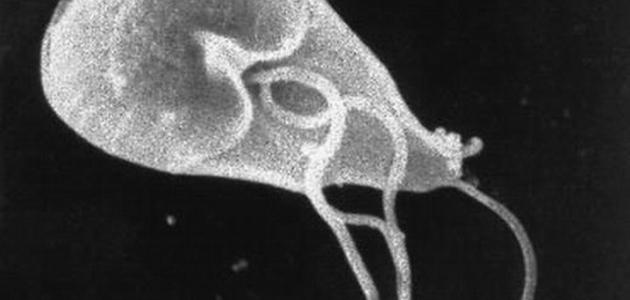

ما هي طفيليات الجيارديا وما أعراض الإصابة بها

عمون - الجيارديا هي طفيليات مجهرية تعيش على سطح التربة والطعام والماء الملوث ببراز الحيوانات أو البشر المصابين بها. تتميز هذه الطفيليات بغلاف خارجي يمكنها من البقاء لفترات طويلة خارج الكائنات الحية وتكون مقاومة للمعقمات المحتوية على الكلور. تسبب الجيارديا مرضًا يعرف بـ "داء الجياردياسيس"، حيث تعيش في الأمعاء وتنتقل إلى البراز. يمكن أن توجد الجيارديا في أي منطقة في الولايات المتحدة وتقدر مراكز مكافحة الأمراض والوقاية منها أن حوالي 16,000 شخص يصابون بها سنوياً في أمريكا.